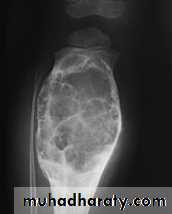

show a radiolucent area situated eccentrically at the end of a long bone and bounded by the sub- chondral bone plate.

The endosteal margin may be quite obvious, but in aggressive lesions it is ill-defined.

X-rays42

The Centre sometimes has a soap-bubble appearance.

The cortex is thin and sometimes ballooned. aggressive lesions extend into the soft tissue.43